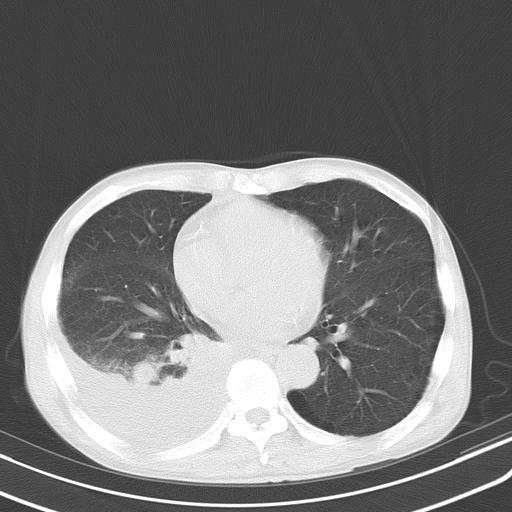

男性 75  咳嗽 一周前发热最高达39

右肺继发型tb并右侧tb性胸腔炎,右侧胸腔大量积液并右下肺膨胀不全,慢支肺气肿、多发肺大泡。建议抽胸水实验室检查并复查排除恶性在占位。

右上肺继发型肺结核,右胸腔中等量积液。

左上肺大泡。

结核的基础上有纵隔淋巴结肿大,右侧有胸水,但右侧纵隔反而窄,说明有肺有不张。

再就是右下肺有块影,和不张混合,还是不能除外肺癌。

补充材料,患者2月份ct片大致正常,双侧胸腔积液,2月份抽胸水未发现ca细胞,现患者发热,痰多,各气管通畅,

1)右肺继发型肺结核。2)左肺胸膜下多发性肺大泡。3)右侧胸腔积液。